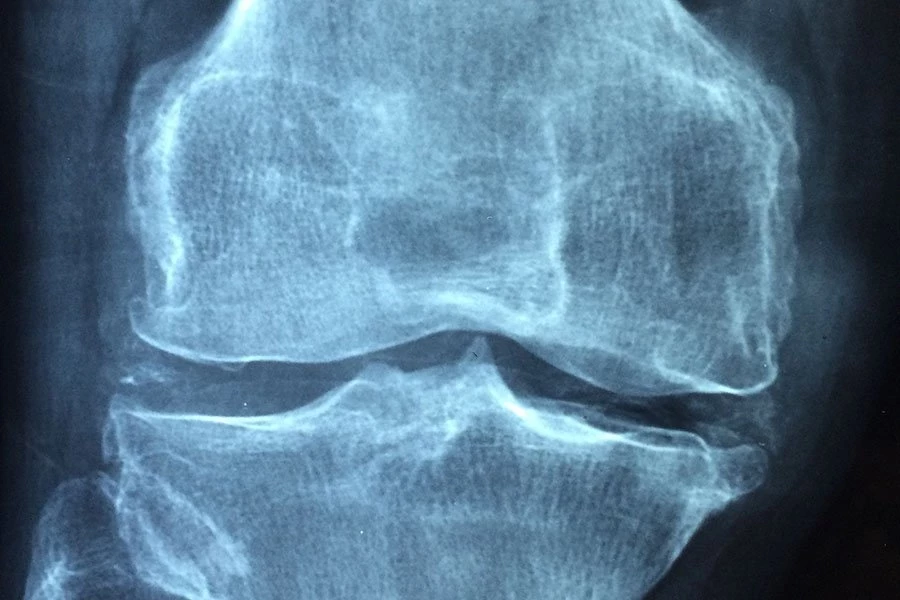

Крупное исследование, опубликованное в журнале открытого доступа RMD Open, показывает, что наличие старших братьев и сестер и удаление миндалин в детстве связано с повышенным риском развития анкилозирующего спондилита (АС), хронического воспалительного артрита. Это подтверждает теорию о том, что детские инфекции могут способствовать возникновению этого состояния, которое вызывает боль, скованность и усталость из-за воспаления позвоночника, суставов и сухожилий.